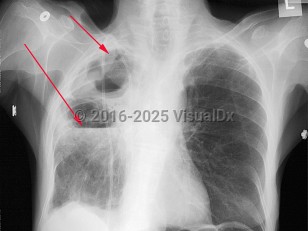

- Bacteremic pneumonia occurs with bloodstream invasion following the onset of respiratory symptoms. This leads to a metastatic spread that results in the embolic lesions seen in the lungs and other viscera. This is followed by alveolar hemorrhage and necrosis, with the patient typically expiring 3-4 days after initial onset.